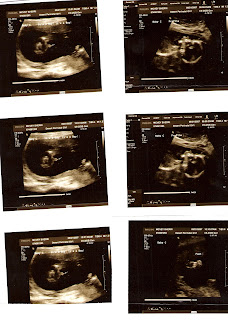

Went to the doctor today and babies are doing great! The photo is of all 3 babies. My cervix length is back to 3 cm, which is very good. Who knew it could contract and expand??? Dr. Bohman says we need to keep doing what we’re doing and that means not much for me. Our doc is optimistic that we can make it to 33 weeks. WOO HOO!!! That will be a projected delivery date of around September 6. It makes me so happy that we are doing the things we need to do to ensure these little monkeys are born as late as possible. Dr. Bohman indicated that we’ll go as long as we can unless someone (either me or one of them) gets distressed or becomes ill. Chip and I also learned today that we will be delivering most likely at Summerlin Hospital, which has the best level III NICU in Las Vegas. It’s 45 minutes away from here, but they need that care and can get it up there. I’ve heard great things about the hospital facility, so that makes me feel good too.